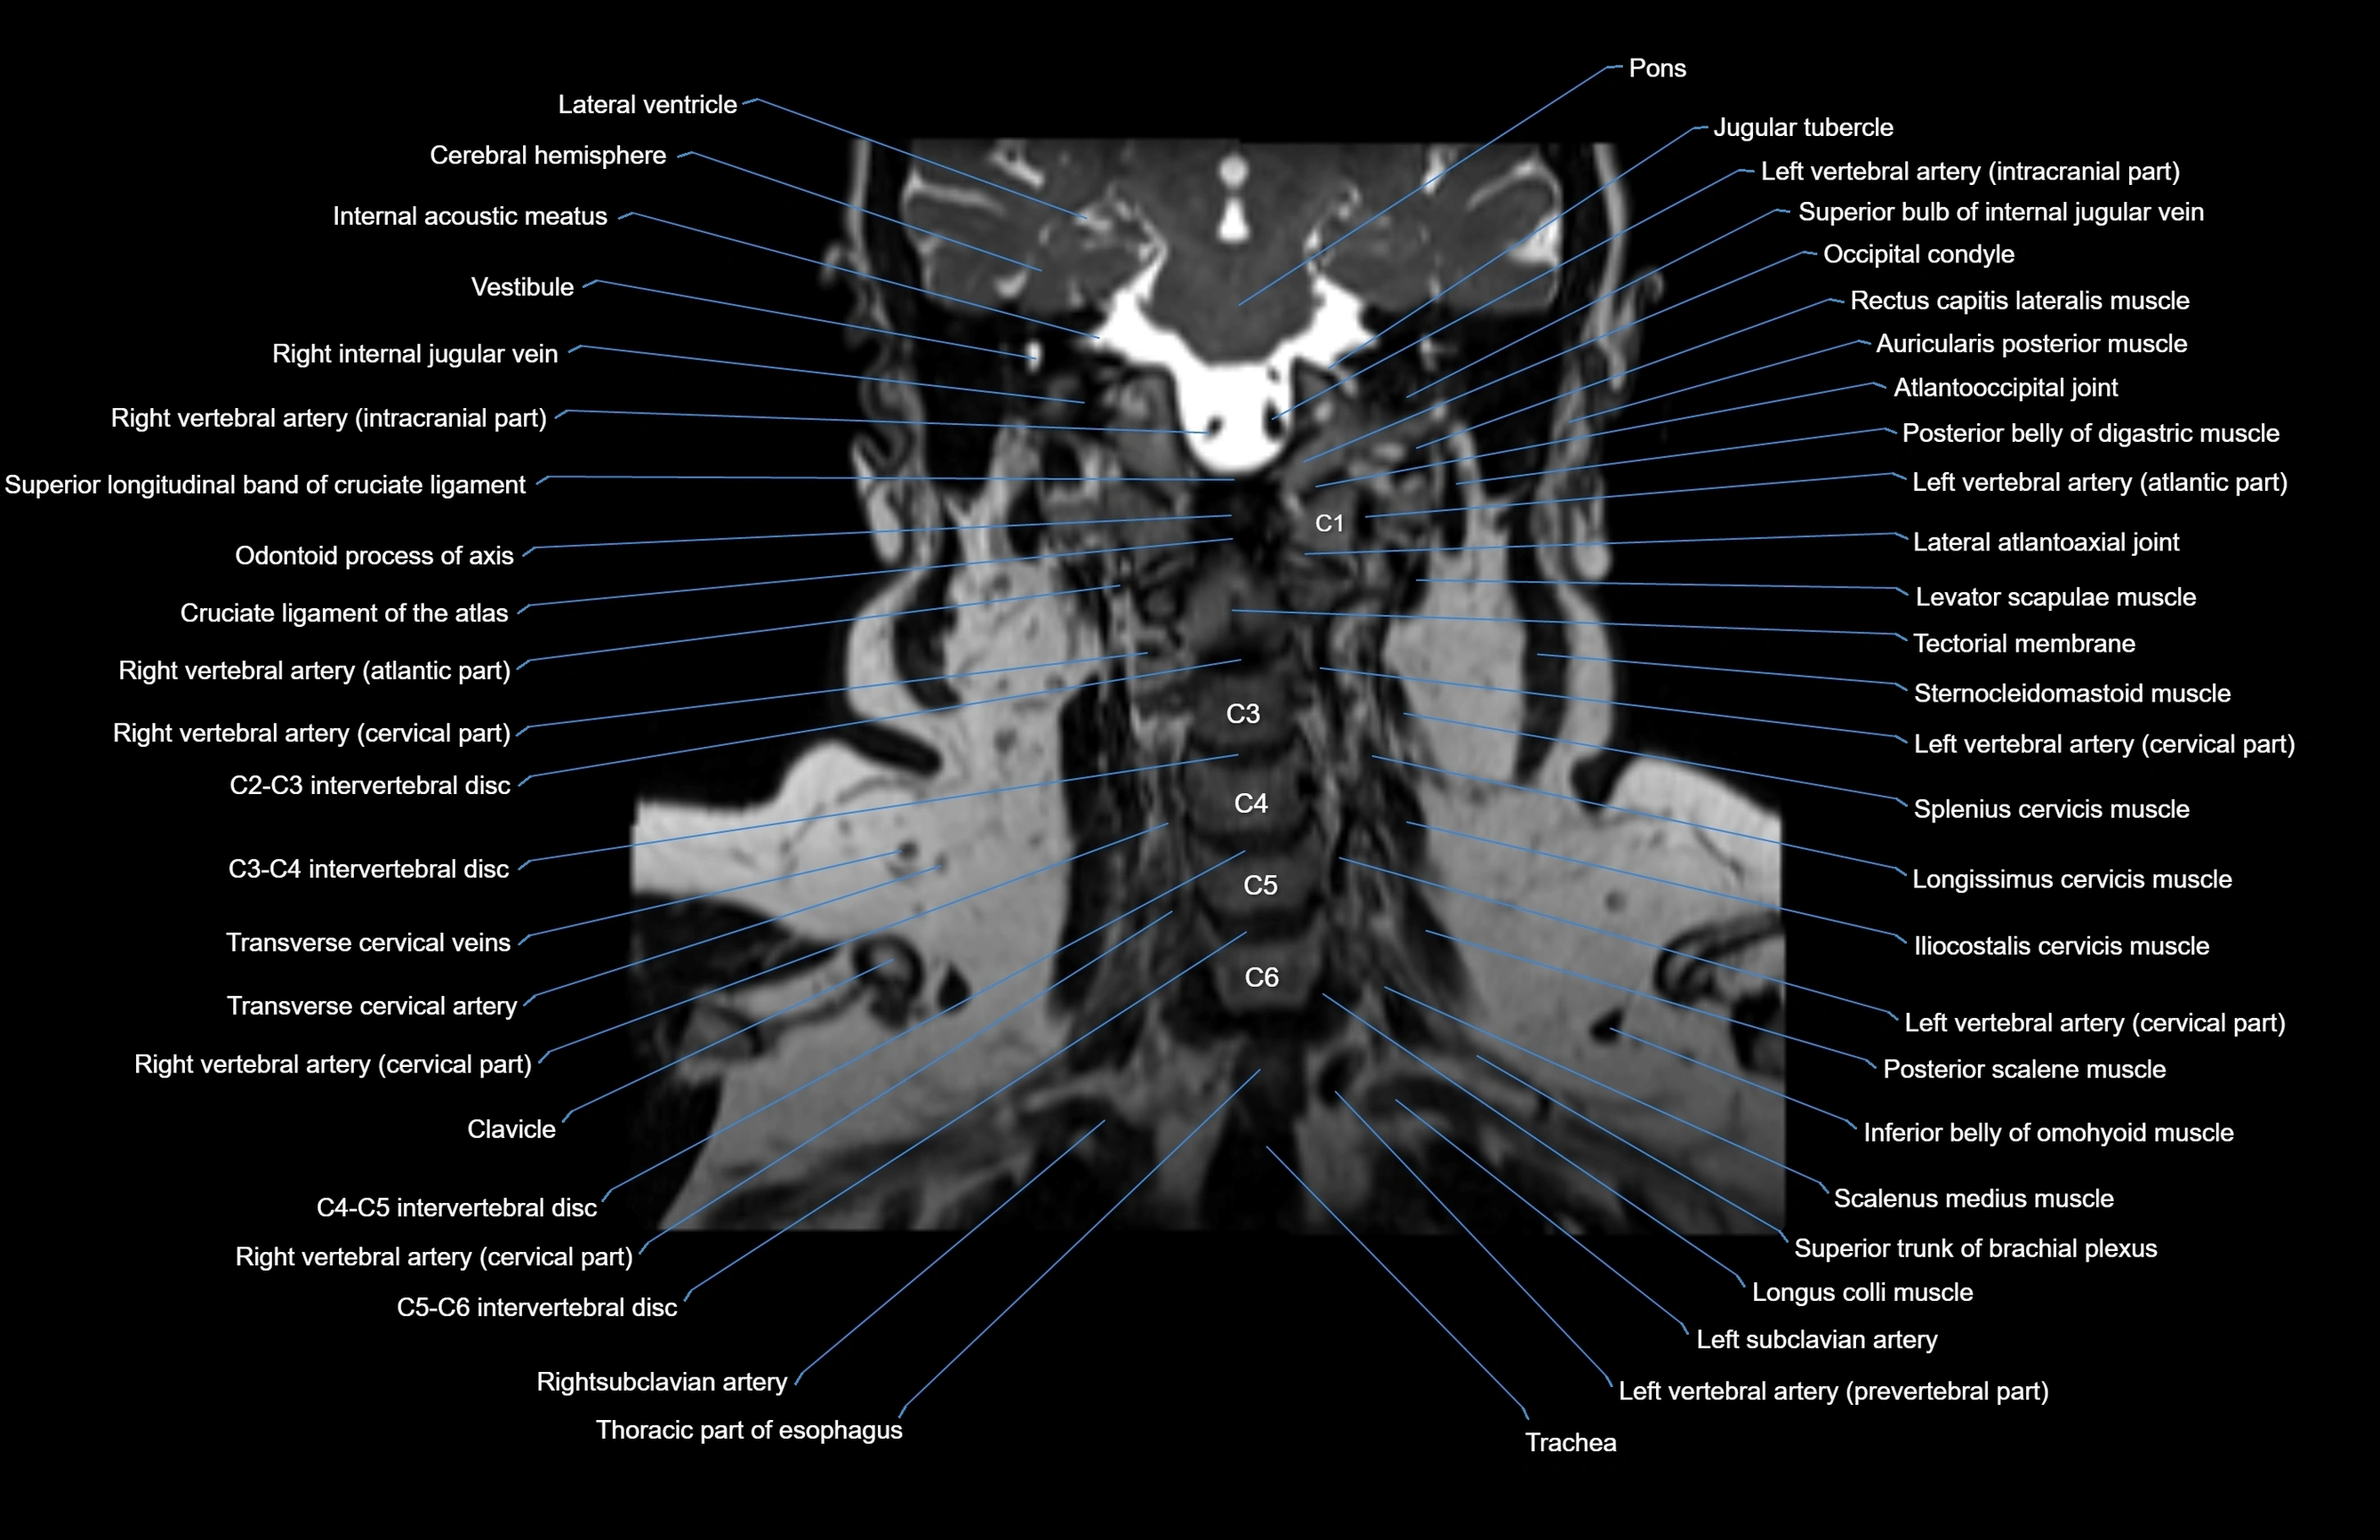

- Atlantooccipital joint

- Cruciate ligament of the atlas

- Iliocostalis cervicis muscle

- Inferior belly of omohyoid muscle

- Lateral atlantoaxial joint

- Left vertebral artery (atlantic part)

- Left vertebral artery (cervical part)

- Levator scapulae muscle

- Longissimus cervicis muscle

- Longus colli muscle

- Occipital condyle

- Right vertebral artery (atlantic part)

- Right vertebral artery (cervical part)

- Scalenus medius muscle (middle scalene muscle)

- Scalenus posterior muscle (Posterior scalene muscle)

- Splenius cervicis muscle

- Sternocleidomastoid muscle

- Superior bulb of internal jugular vein

- Thoracic part of esophagus

- Trachea

- Transverse cervical artery